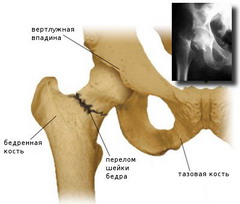

Переломом бедренной кости называется состояние, характеризующееся нарушением ее анатомической целостности. Чаще всего, оно случается у пожилых людей, при падении на бок. Сопутствующими факторами переломов бедра в этих случаях являются сниженный тонус мышц, а также остеопороз.

Признаками перелома являются резкая боль, отечность, нарушение функции и деформация конечности. Вертельные переломы характеризуются более интенсивными болями, которые усиливаются при попытке движения и ощупывании. Основной признак перелома верхней части (шейки) бедра – «симптом прилипшей пятки» – состояние, при котором пациент не может повернуть ногу под прямым углом.

Если переломы являются вколоченными, когда отломок бедренной кости вклинивается в другую кость, практикуется консервативное лечение: больной укладывается на кровать с подложенным под матрац деревянным щитом, при этом поврежденная нога покоится на шине Беллера. Далее осуществляется скелетное вытяжение за мыщелки голени и бедра.

В случае смещенных переломов, характеризующихся деформацией и порочным положением конечности, рекомендуется проведение операции.